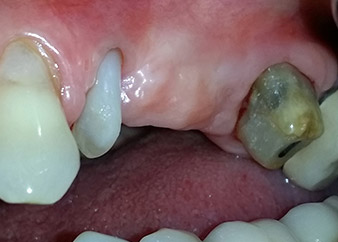

A 58-year-old female patient complained of pain and increased mobility of her bridge abutment tooth 24. Periodontal inflammation was present with pocket depths of 7 mm mesiobuccally and more than 12 mm distally, as well as third-degree furcation involvement. Moreover, the radiograph revealed an extensive periodontal lesion around the apical region of the (alio loco) endodontically pretreated tooth 24 (Fig. 1).

One year earlier, teeth 25 and 26 had been extracted due to trauma and for endo-perio reasons, prior to the placement of the bridge. A combined endo-perio lesion was diagnosed for tooth 24, of unclear aetiology. The patient wanted to keep her bridge abutment teeth 24 and 27 and would not accept a final, or even temporary, removable prosthesis. Therefore, it was agreed to make all efforts to retain both teeth, in spite of their poor prognosis as based on radiological and clinical findings.

One month later, on the day of surgery, pain and inflammation at tooth 24 were minimal, but mobility of Miller class 2 was still present. After opening the flaps and cleaning the periapical and peri radicular infected tissue, the extent of the bone defect became obvious (Figs. 2 and 3).

At the buccal root, all vestibular and distal bone was missing. Attachment was essentially restricted to the palatal root, underlining the preliminary poor prognosis. Tooth 27 also showed a reduced horizontal attachment and a minimal apical rarefaction (cf. Fig. 1) without clinical symptoms.